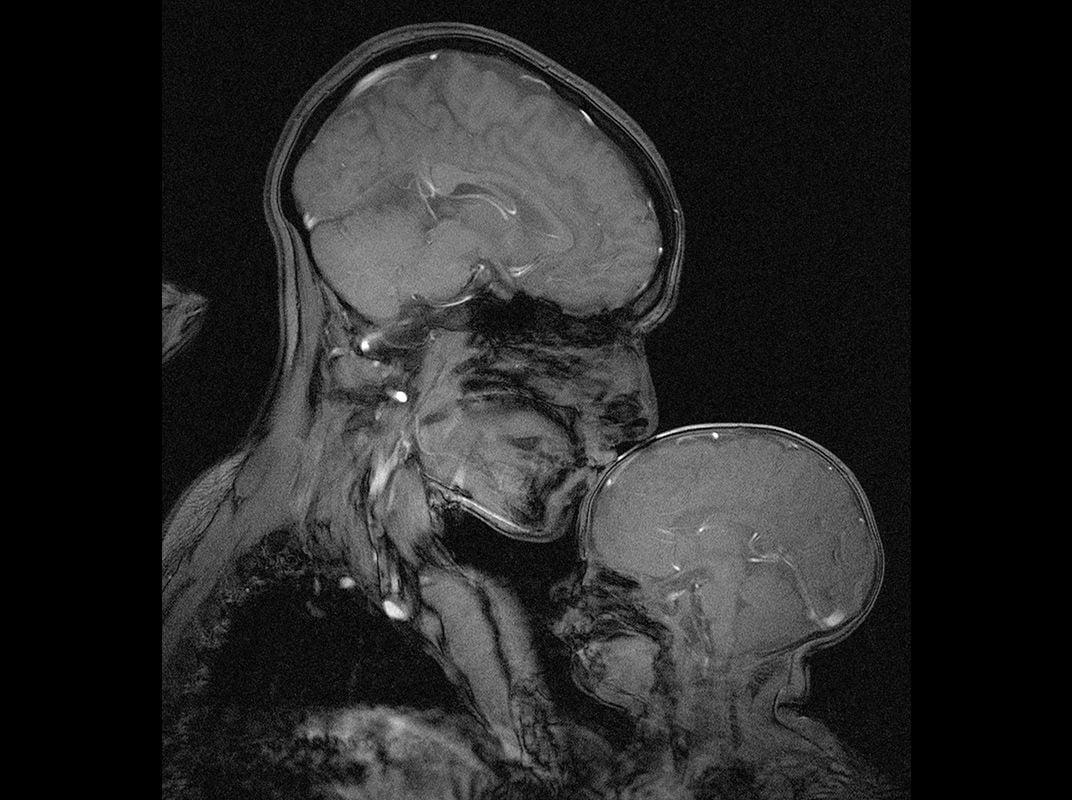

EditorLa neuróloga Rebecca Saxe presentó la “foto” más hermosa del año. Es la imagen de una resonancia magnética captada cuando una madre besa a su hijo de dos meses. Los labios colocados en la cabeza del pequeño inmediatamente provocan una reacción en su cerebro.

Se libera dopamina, que da la sensación de bienestar, pero también oxitocina, bautizada como la hormona de amor, porque es responsable del afecto y el apego.

Besar provoca una reacción química en el cerebro del pequeño. Reduce el miedo y aumenta la confianza, provoca sentimientos de afecto y apego, señal de que el bebé entendió que está protegido.

También se libera vasopresina, el ′′ pegamento ′′ que conecta madres con bebés en sus primeros meses de vida y serotonina, que regula el estado de ánimo.